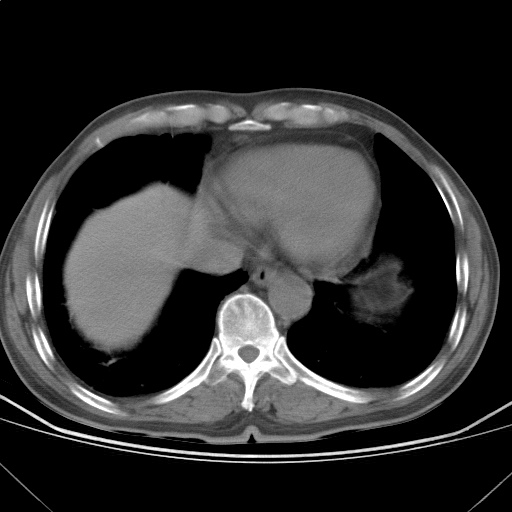

以下是引用随光逐影在2009-5-1 13:53:00的发言:[br]考虑为:1)两肺血行播散型肺结核;2)右肺下叶炎症感染。3)右侧胸膜增厚。